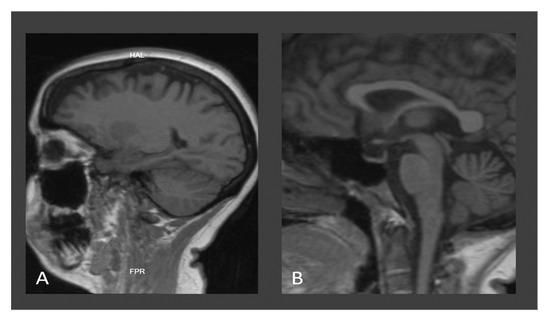

| Neuroimaging for W.D. | Typical | Typical | Typical |